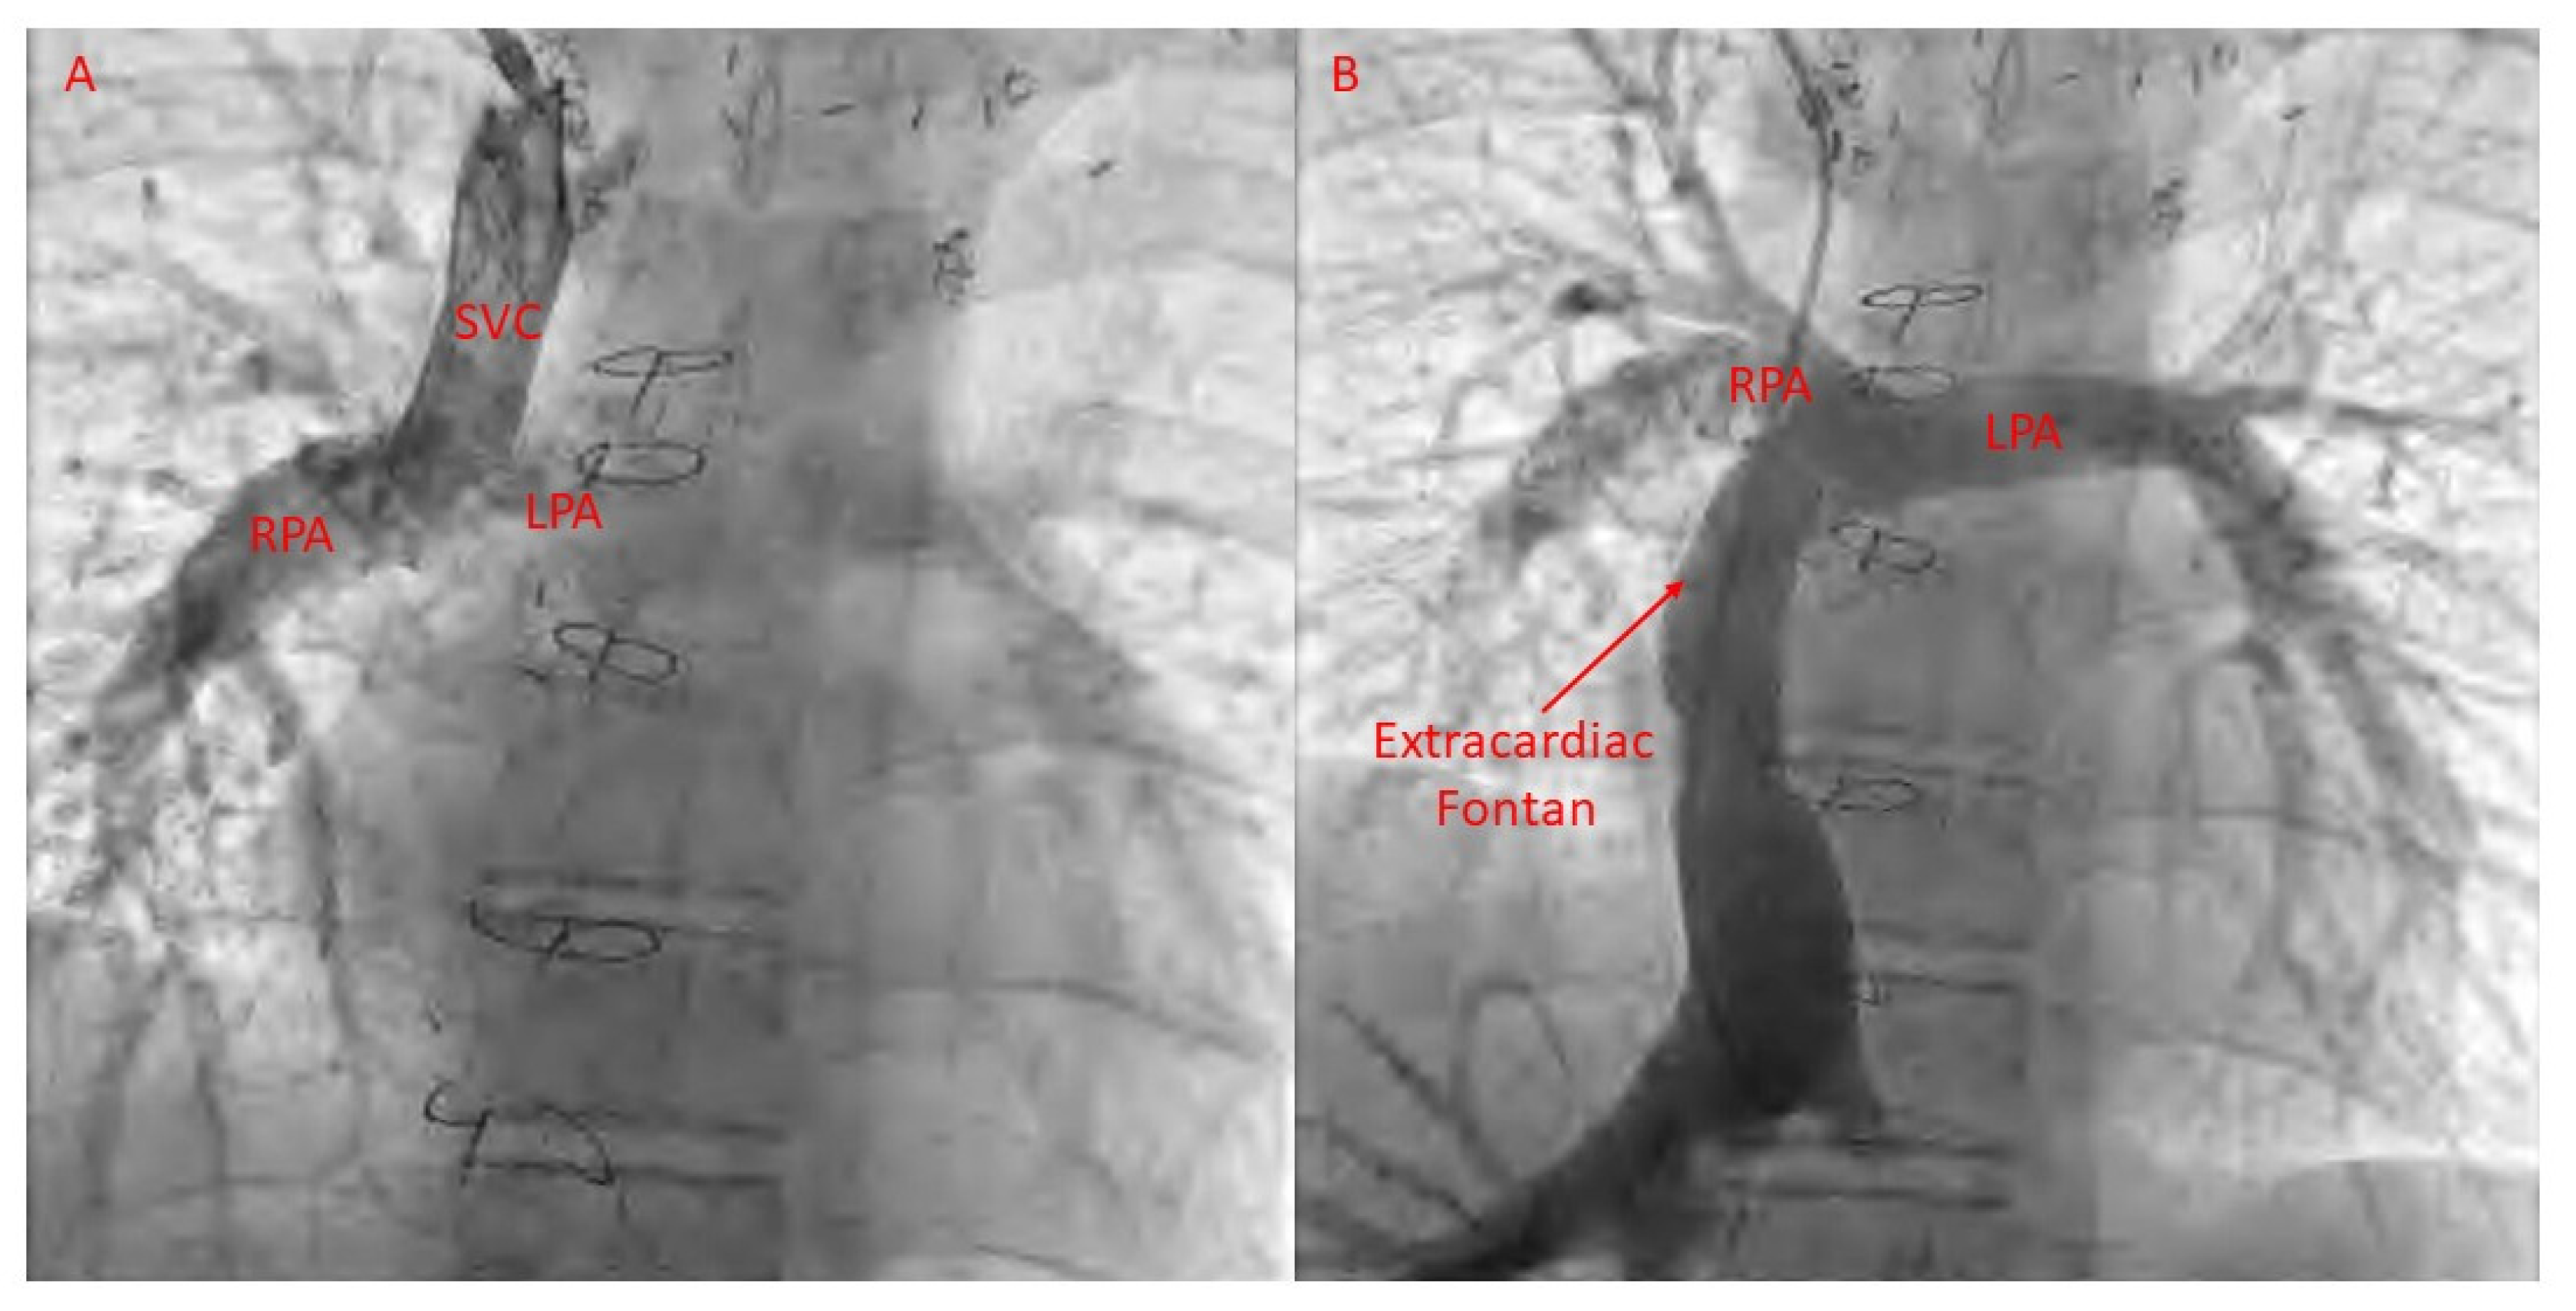

20. Transplantation

22. Fontan Pathway Obstruction